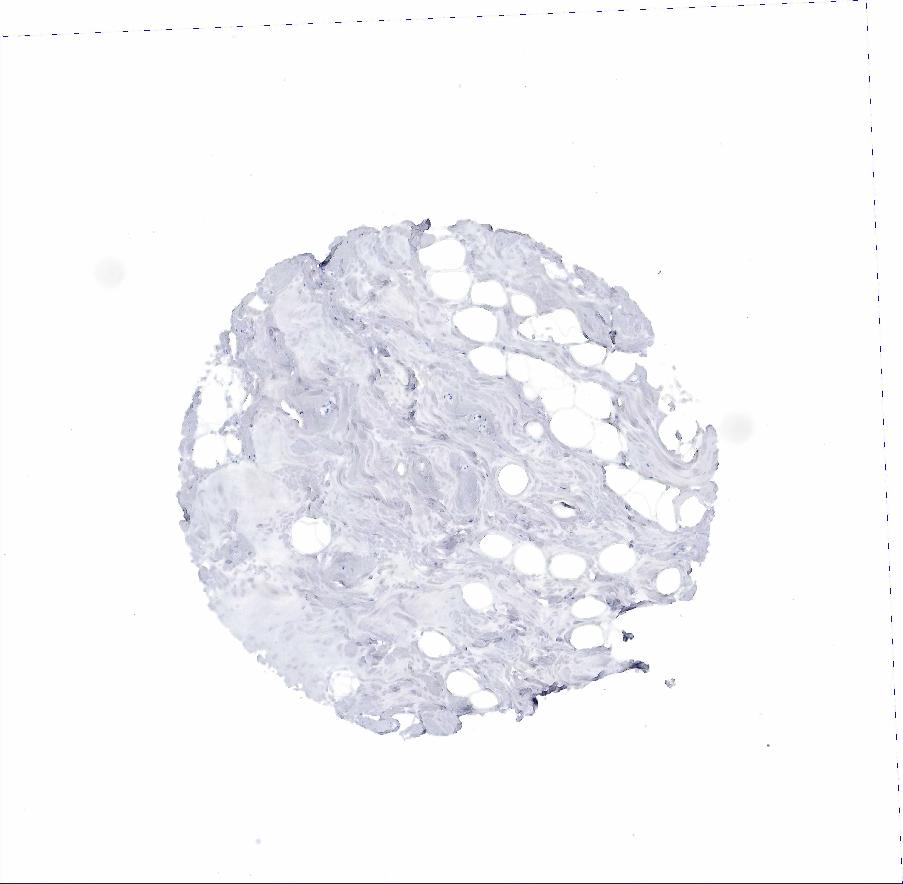

ADIPOSE TISSUE - Antibody stainingi

Antibody staining in the annotated cell types in the current human tissue is reported as not detected, low, medium, or high, based on conventional immunohistochemistry profiling in selected tissues. This score is based on the combination of the staining intensity and fraction of stained cells.

Each image is clickable and will lead to virtual microscopy that enables deeper exploration of all samples and also displays staining intensity scores, fraction scores and subcellular localization as well as patient and tissue information for each sample.

Antibody HPA002465Antibody CAB000031

Adipocytes Not detectedNot detected